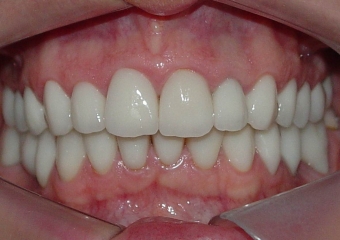

Sorriso final